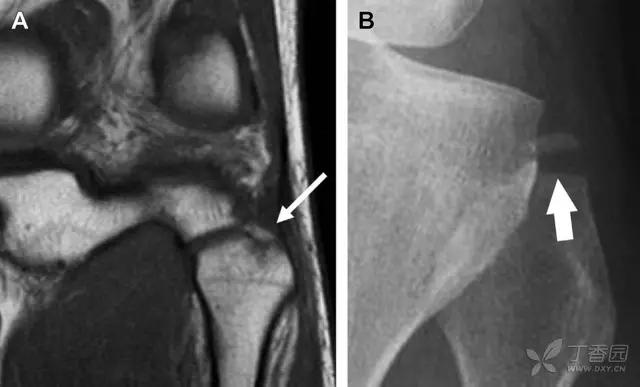

13 腓骨茎突撕脱性骨折

为胫骨前内侧受到直接*力暴**作用,发生在腓骨茎突的横形骨折,可表现为弓形信号(图 6)。可伴发前交叉韧带或后交叉韧带的断裂。如果弓形信号被忽视或未处理,前交叉韧带的重建将失败。

图 6 跌倒后发生腓骨茎突骨折

A MRI 冠状位 T1 加权像示腓骨茎突撕脱性骨折(箭头)。弓状韧带附着于骨折碎片,而联合腱绕过外侧附着于其上。B 正位片见横形骨折线(箭头)。